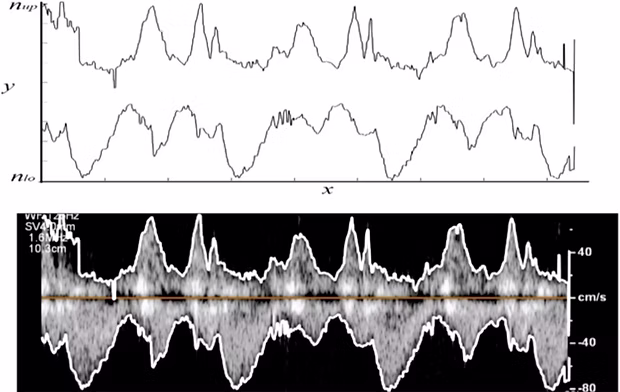

Khalili, F., Gamage, P.T., Taebi, A., Johnson, M.E., Roberts, R.B., Mitchell, J. (2021).

Spectral decomposition of the flow and characterization of the sound signals generated through stenoses of different levels of severity.

Bioengineering, 8(3): 41.

equiHeart Project

Spectral decomposition and sound source localization of highly disturbed flow through a severe arterial stenosis.

Bioengineering, 8(3): 34.

Taebi, A., Sandler, R.H., Kakavand, B., Mansy, H.A. (2019).

Extraction of Peak Velocity Profiles from Doppler Echocardiography Using Image Processing.

Bioengineering, 6(3): 64.

Taebi, A., Mansy, H.A. (2017).

Time-frequency Distribution of Seismocardiographic Signals: A Comparative Study.

Bioengineering, 4(2): 32.

Noise Cancellation from Vibrocardiographic Signals Based on the Ensemble Empirical Mode Decomposition.

Journal of Applied Biotechnology and Bioengineering, 2(2): 00024.

Taebi, A., Mansy, H.A. (2016).

Effect of noise on time-frequency analysis of Vibrocardiographic signals.

Journal of Bioengineering and Biomedical Science, 6(202), 2.